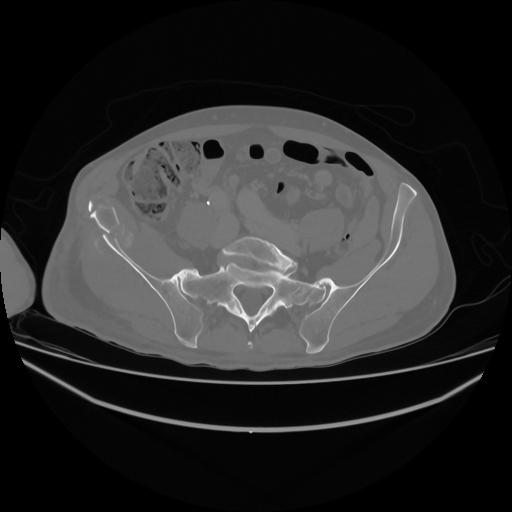

5 CUERPO,CE,Vol,1.0,CUERPO,,